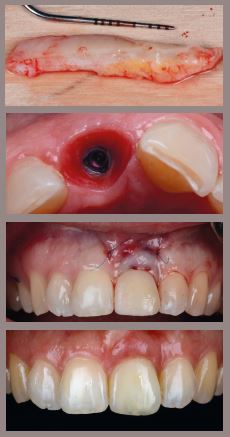

• Surgical Veneer Graft

CRITICAL SOFT TISSUE GRAFTING

LECTURE TOPICS

• Tissue biology and gingiva phenotypes

• Zero Bone Loss Concept

• Ridge augmentation by Tissue Grafting

• Flap designs and harvesting techniques

• Mastering Suturing (micro-sutures)

• Root coverage: Flap, Tunnel, VISTA ?

• Gold Standard (CTG) or Allograft ?

HANDS-ON:

1. Harvesting and suturing exercise on pig jaw / soft tissue model

2. Ridge augmentation (Roll- technique, inlay-, onlay graft)

3. Root coverage